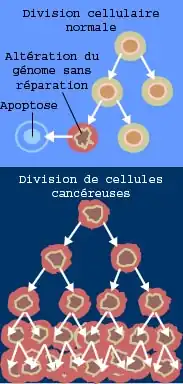

Transformation cancéreuse

Evolution du cancer

La cancérogenèse est fondamentalement un processus évolutif[54], faisant intervenir des processus darwiniens et non darwiniens tels que la mutation, la dérive génétique et la sélection clonale, en particulier sur les oncogènes et les gènes suppresseurs de tumeur, ainsi que des processus de dédoublement du génome et d’anomalies chromosomiques[55],[56]. La carcinogenèse peut également être comparée à un événement de spéciation[57].

Cancérogenèse

Le stade cancérogenèse de la transformation cancéreuse nécessite deux étapes : l'initiation et la promotion. Ces deux étapes sont obligatoirement successives et l'initiation précède toujours la promotion, sans quoi le processus cancéreux s'arrête.

Initiation

L'initiation correspond à l'accumulation des anomalies génétiques.

L'initiation (ou transformation cellulaire) comporte deux éléments majeurs :

- l'immortalisation : les cellules deviennent incapables d'initier leur propre mort (apoptose) ou ne répondent plus aux signaux extérieurs qui la déclenchent[67],[68];

- la perte d'homéostasie. L'homéostasie est caractérisée normalement par un équilibre divisions/morts qui assure le maintien de la taille et de la fonctionnalité d'un organe. Dans notre cas, les cellules cancéreuses perdent la sensibilité aux signaux qui régulent la prolifération.

L'initiation est la conséquence de la carcinogenèse. L'action des carcinogènes mute des gènes importants dans le maintien de l'intégrité et des caractéristiques de chaque type cellulaire.

Il en résulte des pertes ou gains de fonctions cellulaires :

- activation ou dérépression d'un proto-oncogène : les proto-oncogènes (appelés oncogènes lorsqu'ils sont mutés) sont souvent des activateurs de la multiplication ou des inhibiteurs de l'apoptose (BCL, BCLX1, etc.) ;

- inhibition ou répression d'un gène suppresseur de tumeur aussi appelés anti-oncogènes : les gènes suppresseurs sont des inducteurs de l'apoptose ou des bloqueurs du cycle cellulaire (P53, BAC, etc.).

Promotion

La promotion recouvre la réception par la cellule de facteurs de prolifération qui vont entraîner les divisions. Ces signaux vont donc pérenniser les anomalies au cours des divisions, et ainsi assurer la descendance de la cellule anormale, qui va de surcroît accumuler de nouvelles anomalies génétiques (voir Transformation cellulaire).

La promotion est caractérisée par une grande instabilité génomique et une augmentation de la perte d'homéostasie.

L'instabilité génomique est due à des mutations de deux types de gènes :

- les gènes portiers (gate keeper genes) : ils assurent le contrôle du passage à une étape ultérieure du cycle cellulaire. Une perte de fonction de ces gènes permet à la cellule cancéreuse de passer rapidement à la phase ultérieure du cycle cellulaire, donc in fine de proliférer de façon incontrôlée ;

- les gènes soignants (care taker genes) : ils assurent physiologiquement la réparation des anomalies liées à l'ADN. Leur inactivation entraîne une instabilité accrue et une accumulation d'anomalies génétiques (mutation, perte d'hétérozygotie, modifications épigénétiques, aussi dénommées « épimutation » : hypo/hyperméthylation, désacétylation, etc.).

Ces points de contrôle et de réparation altérés, la cellule cancéreuse a désormais perdu la capacité à « reconnaître sa vieillesse », initier sa mort et réparer les dommages de son ADN. La réponse aux signaux de croissance physiologiques est en outre disproportionnée.

Ensuite, la cellule commence à produire ses propres signaux de prolifération (cf. infra) : la croissance incontrôlée d'un pool de cellules n'a alors plus de limite.